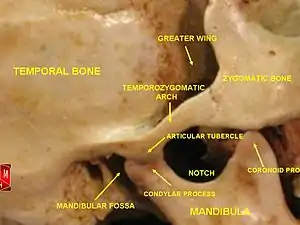

Structure

The main components are the joint capsule, articular disc, mandibular condyles, articular surface of the temporal bone, temporomandibular ligament, stylomandibular ligament, sphenomandibular ligament, and lateral pterygoid muscle.

The articular capsule (capsular ligament) is a thin, loose envelope, attached above to the circumference of the mandibular fossa and the articular tubercle immediately in front; below, to the neck of the condyle of the mandible. Its loose attachment to the neck of the mandible allows for free movement.

Each temporomandibular joint is classed as a "ginglymoarthrodial" joint since it is both a ginglymus (hinging joint) and an arthrodial (sliding) joint.[13] The condyle of the mandible articulates with the temporal bone in the mandibular fossa. The mandibular fossa is a concave depression in the squamous portion of the temporal bone.

These two bones are actually separated by an articular disc, which divides the joint into two distinct compartments. The inferior compartment allows for rotation of the condylar head around an instantaneous axis of rotation,[14] corresponding to the first 20mm or so of the opening of the mouth. After the mouth is open to this extent, the mouth can no longer open without the superior compartment of the temporomandibular joints becoming active.

At this point, if the mouth continues to open, not only are the condylar heads rotating within the lower compartment of the temporomandibular joints, but the entire apparatus (condylar head and articular disc) translates. Although this had traditionally been explained as a forward and downward sliding motion, on the anterior concave surface of the mandibular fossa and the posterior convex surface of the articular eminence, this translation actually amounts to a rotation around another axis. This effectively produces an evolute which can be termed the resultant axis of mandibular rotation, which lies in the vicinity of the mandibular foramen, allowing for a low-tension environment for the vasculature and innervation of the mandible.[14]